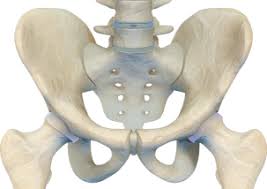

고관절 통증이 나타나는 위치

고관절 통증은 엉덩이 깊숙한 부위에서만 느껴진다고 생각하기 쉽지만, 실제로는 다양한 위치로 퍼져 나타날 수 있습니다.